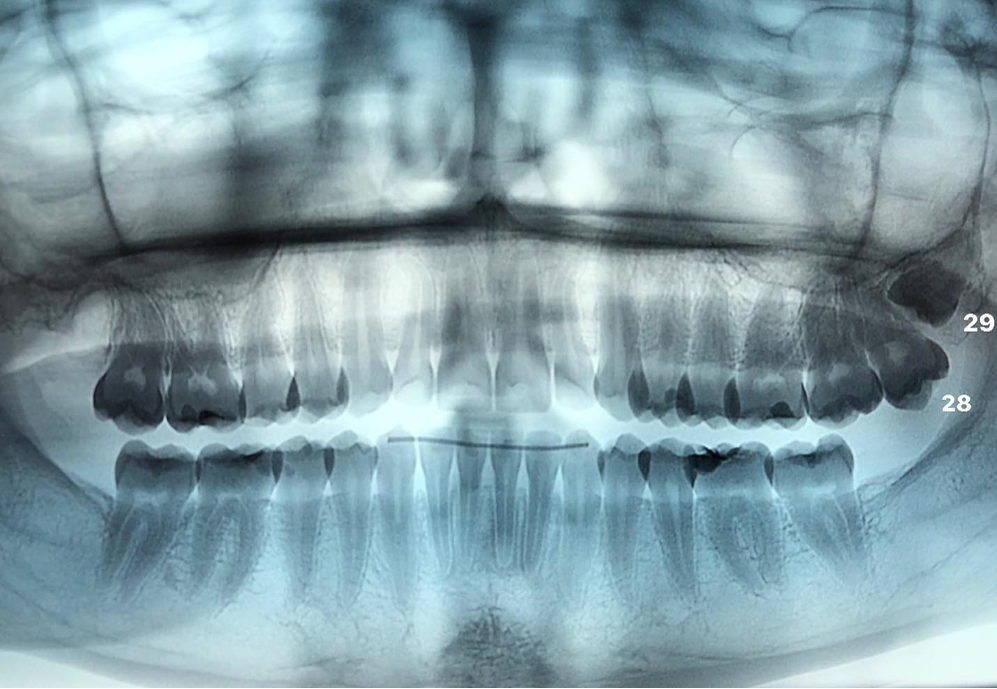

Estrazione di denti del giudizio . È l’intervento più frequente in chirurgia orale. Tra le indicazioni per l’avulsione possiamo menzionare la mancanza di spazio nella mascella o nella mandibola per la sua corretta eruzione, il suo orientamento anomalo responsabile di infiammazioni alle mucose o danni ai molari vicini, le necessità ortodontiche.

Estrazioni dentali complesse. Un’estrazione dentale può essere complicata non solo da un punto di vista pratico chirurgico ma anche nella gestione di casi in cui i pazienti assumono farmaci o presentano malattie sistemiche.